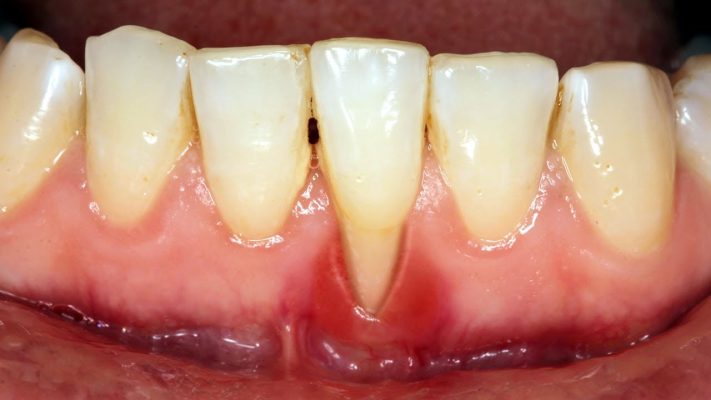

5. Gum Recession

Gums pulling away from the teeth expose the roots, making teeth look longer and more sensitive to temperature.

If untreated, gum disease progresses from gingivitis to periodontitis, where the infection begins damaging the bone and supporting tissues.

1. Deep Gum Pockets

Spaces form between your teeth and gums, trapping bacteria and food particles.

Dentists measure this pocket depth during periodontal exams — anything deeper than 3mm suggests disease.